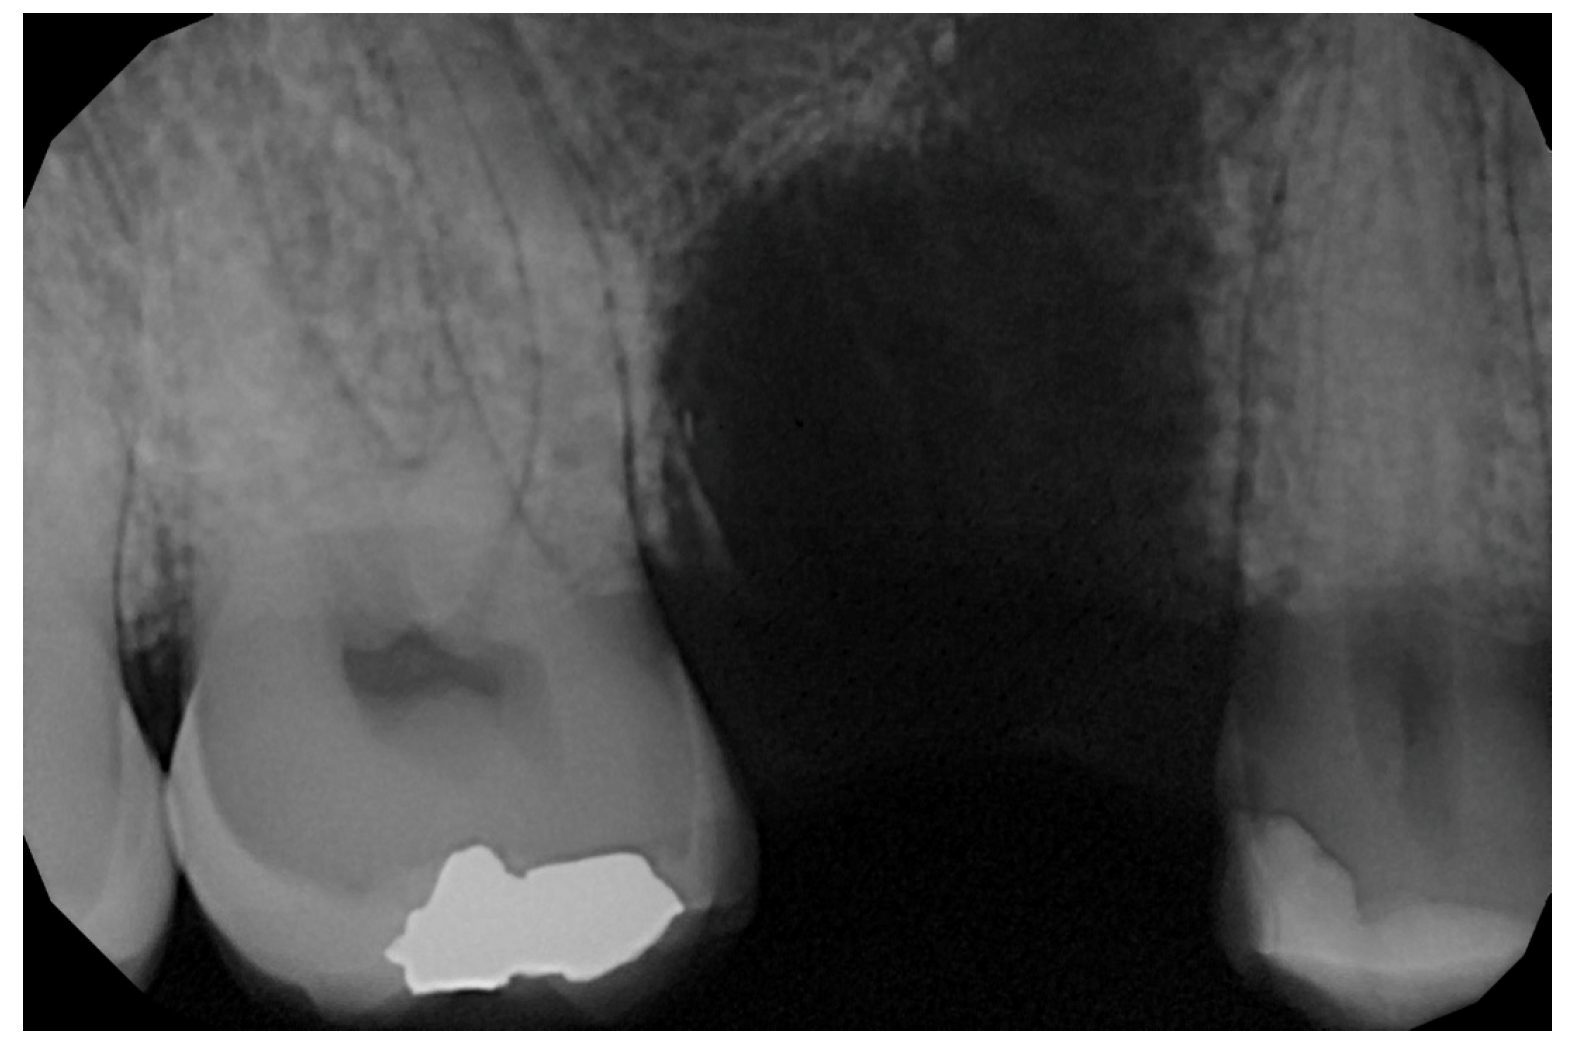

2.6. Case Presentation. Nano-HA Applied to Socket Preservation Procedures

3. Results